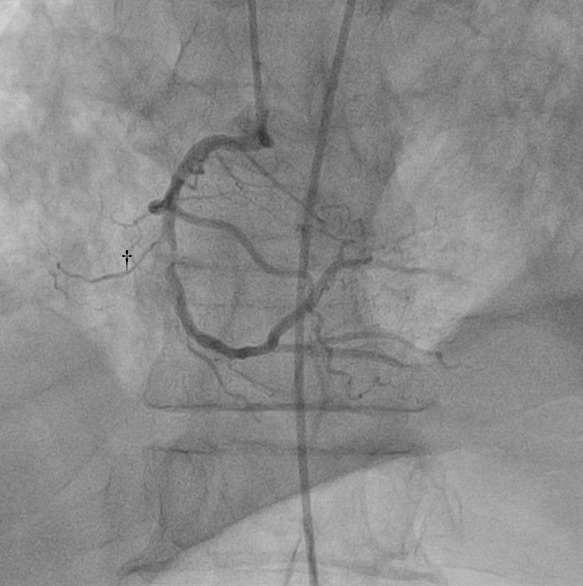

2. Arteria coronaria derecha: se observó una lesión en el segmento medio, excéntrica, con carga de trombo, con estenosis de 99% y flujo distal TIMI 2 (Ver Figura 3)